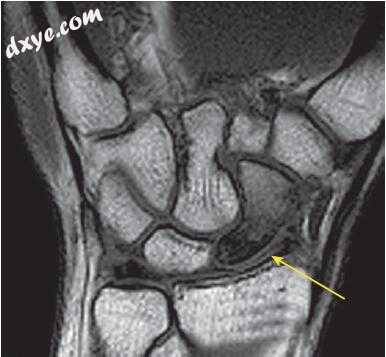

19,c.jpg

图.19, 结  H, 术后6个月术后活动范围。